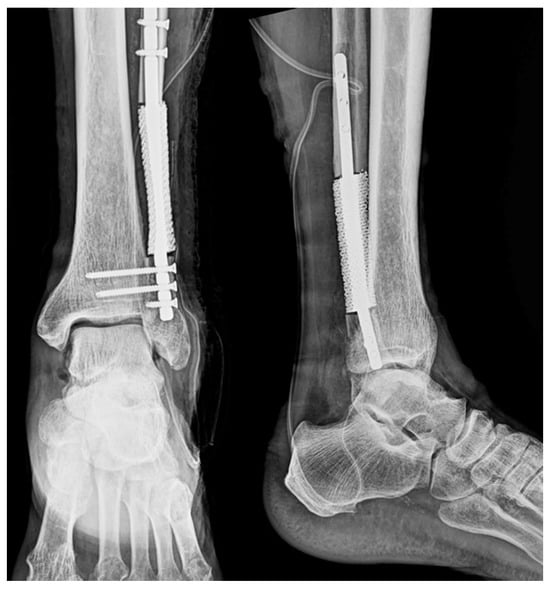

Postoperative radiographs showed accurate prosthesis placement and stable fixation with preservation of anatomical alignment (Figure 11). Although the surgery was successful, the patient experienced recurrence of the primary lung cancer three months after the operation and succumbed to obstructive pneumonia five months after surgery. Due to the patient’s metastatic disease, postoperative functional improvement was limited. However, radiographs confirmed accurate prosthesis alignment and stable fixation. Bone integration could not be assessed due to the patient’s limited survival period.

Figure 11. Postoperative imaging. Postoperative radiographs of the ankle in anteroposterior and lateral views showing stable intramedullary prosthesis fixation and proper alignment.